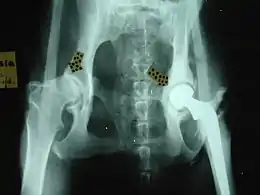

X-ray of a dog with an artificial hip to repair hip dysplasia